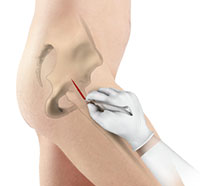

Arthroscopy, also referred to as keyhole or minimally invasive surgery, is a procedure in which an arthroscope is inserted into a joint to check for any damage and repair it simultaneously.